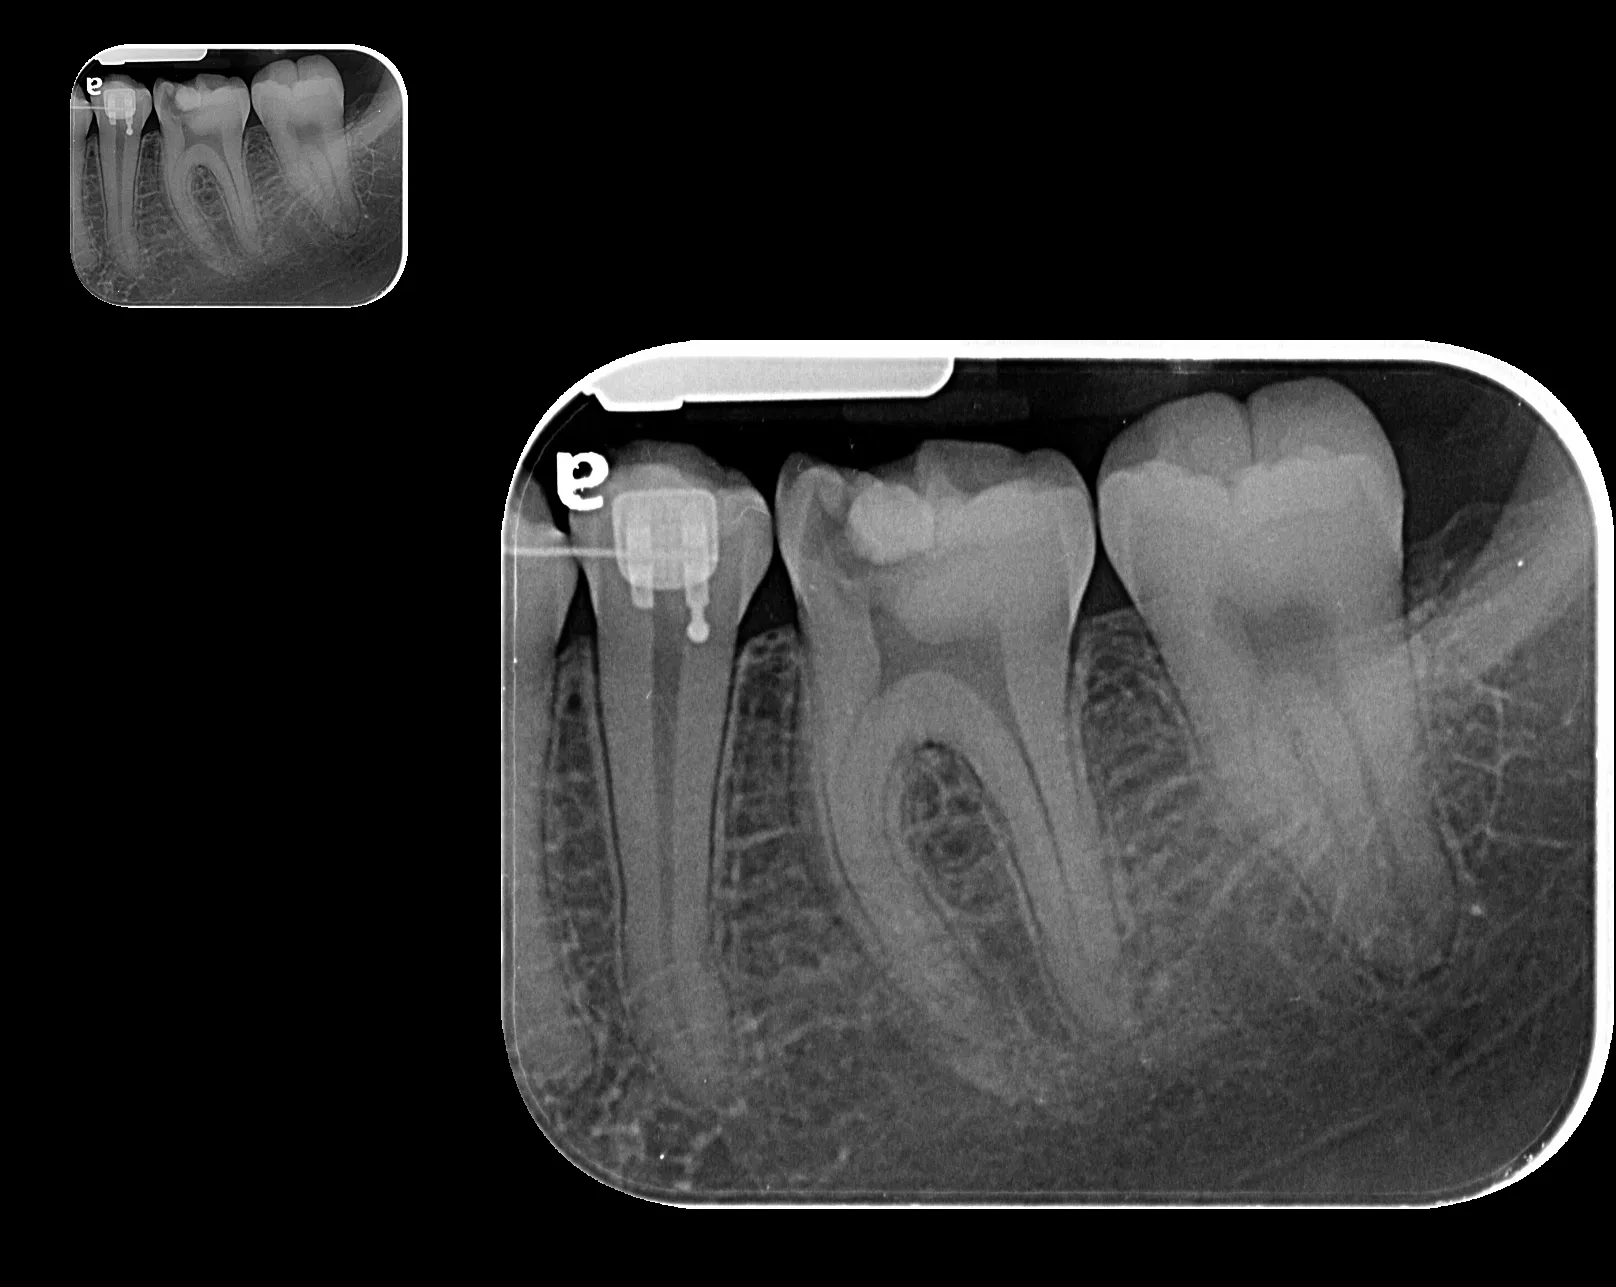

Radiografía Intraoral

La radiografía intraoral permite observar con gran detalle los dientes y las estructuras que los rodean. Es una herramienta fundamental para detectar caries, infecciones, fracturas, alteraciones en la raíz dental o en el hueso de soporte.

• Ideal para tratamientos de endodoncia, implantología y control preventivo.